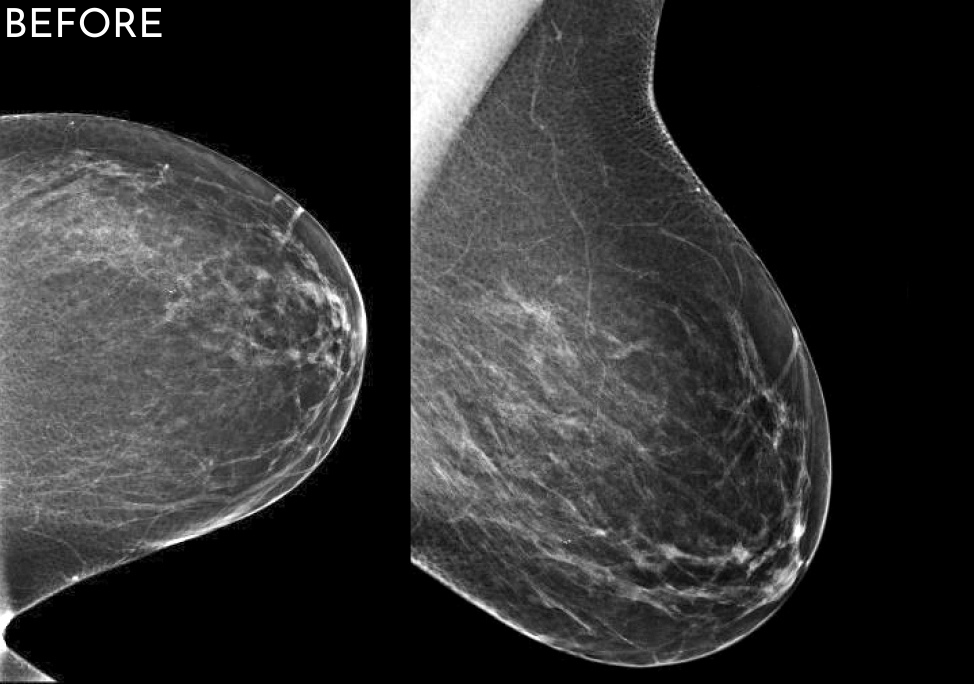

When comparing “before” and “after” images, the improvement can often be startling, even if the original images were really good! We have even identified cancers that were not visualized the year prior. Now that is amazing!